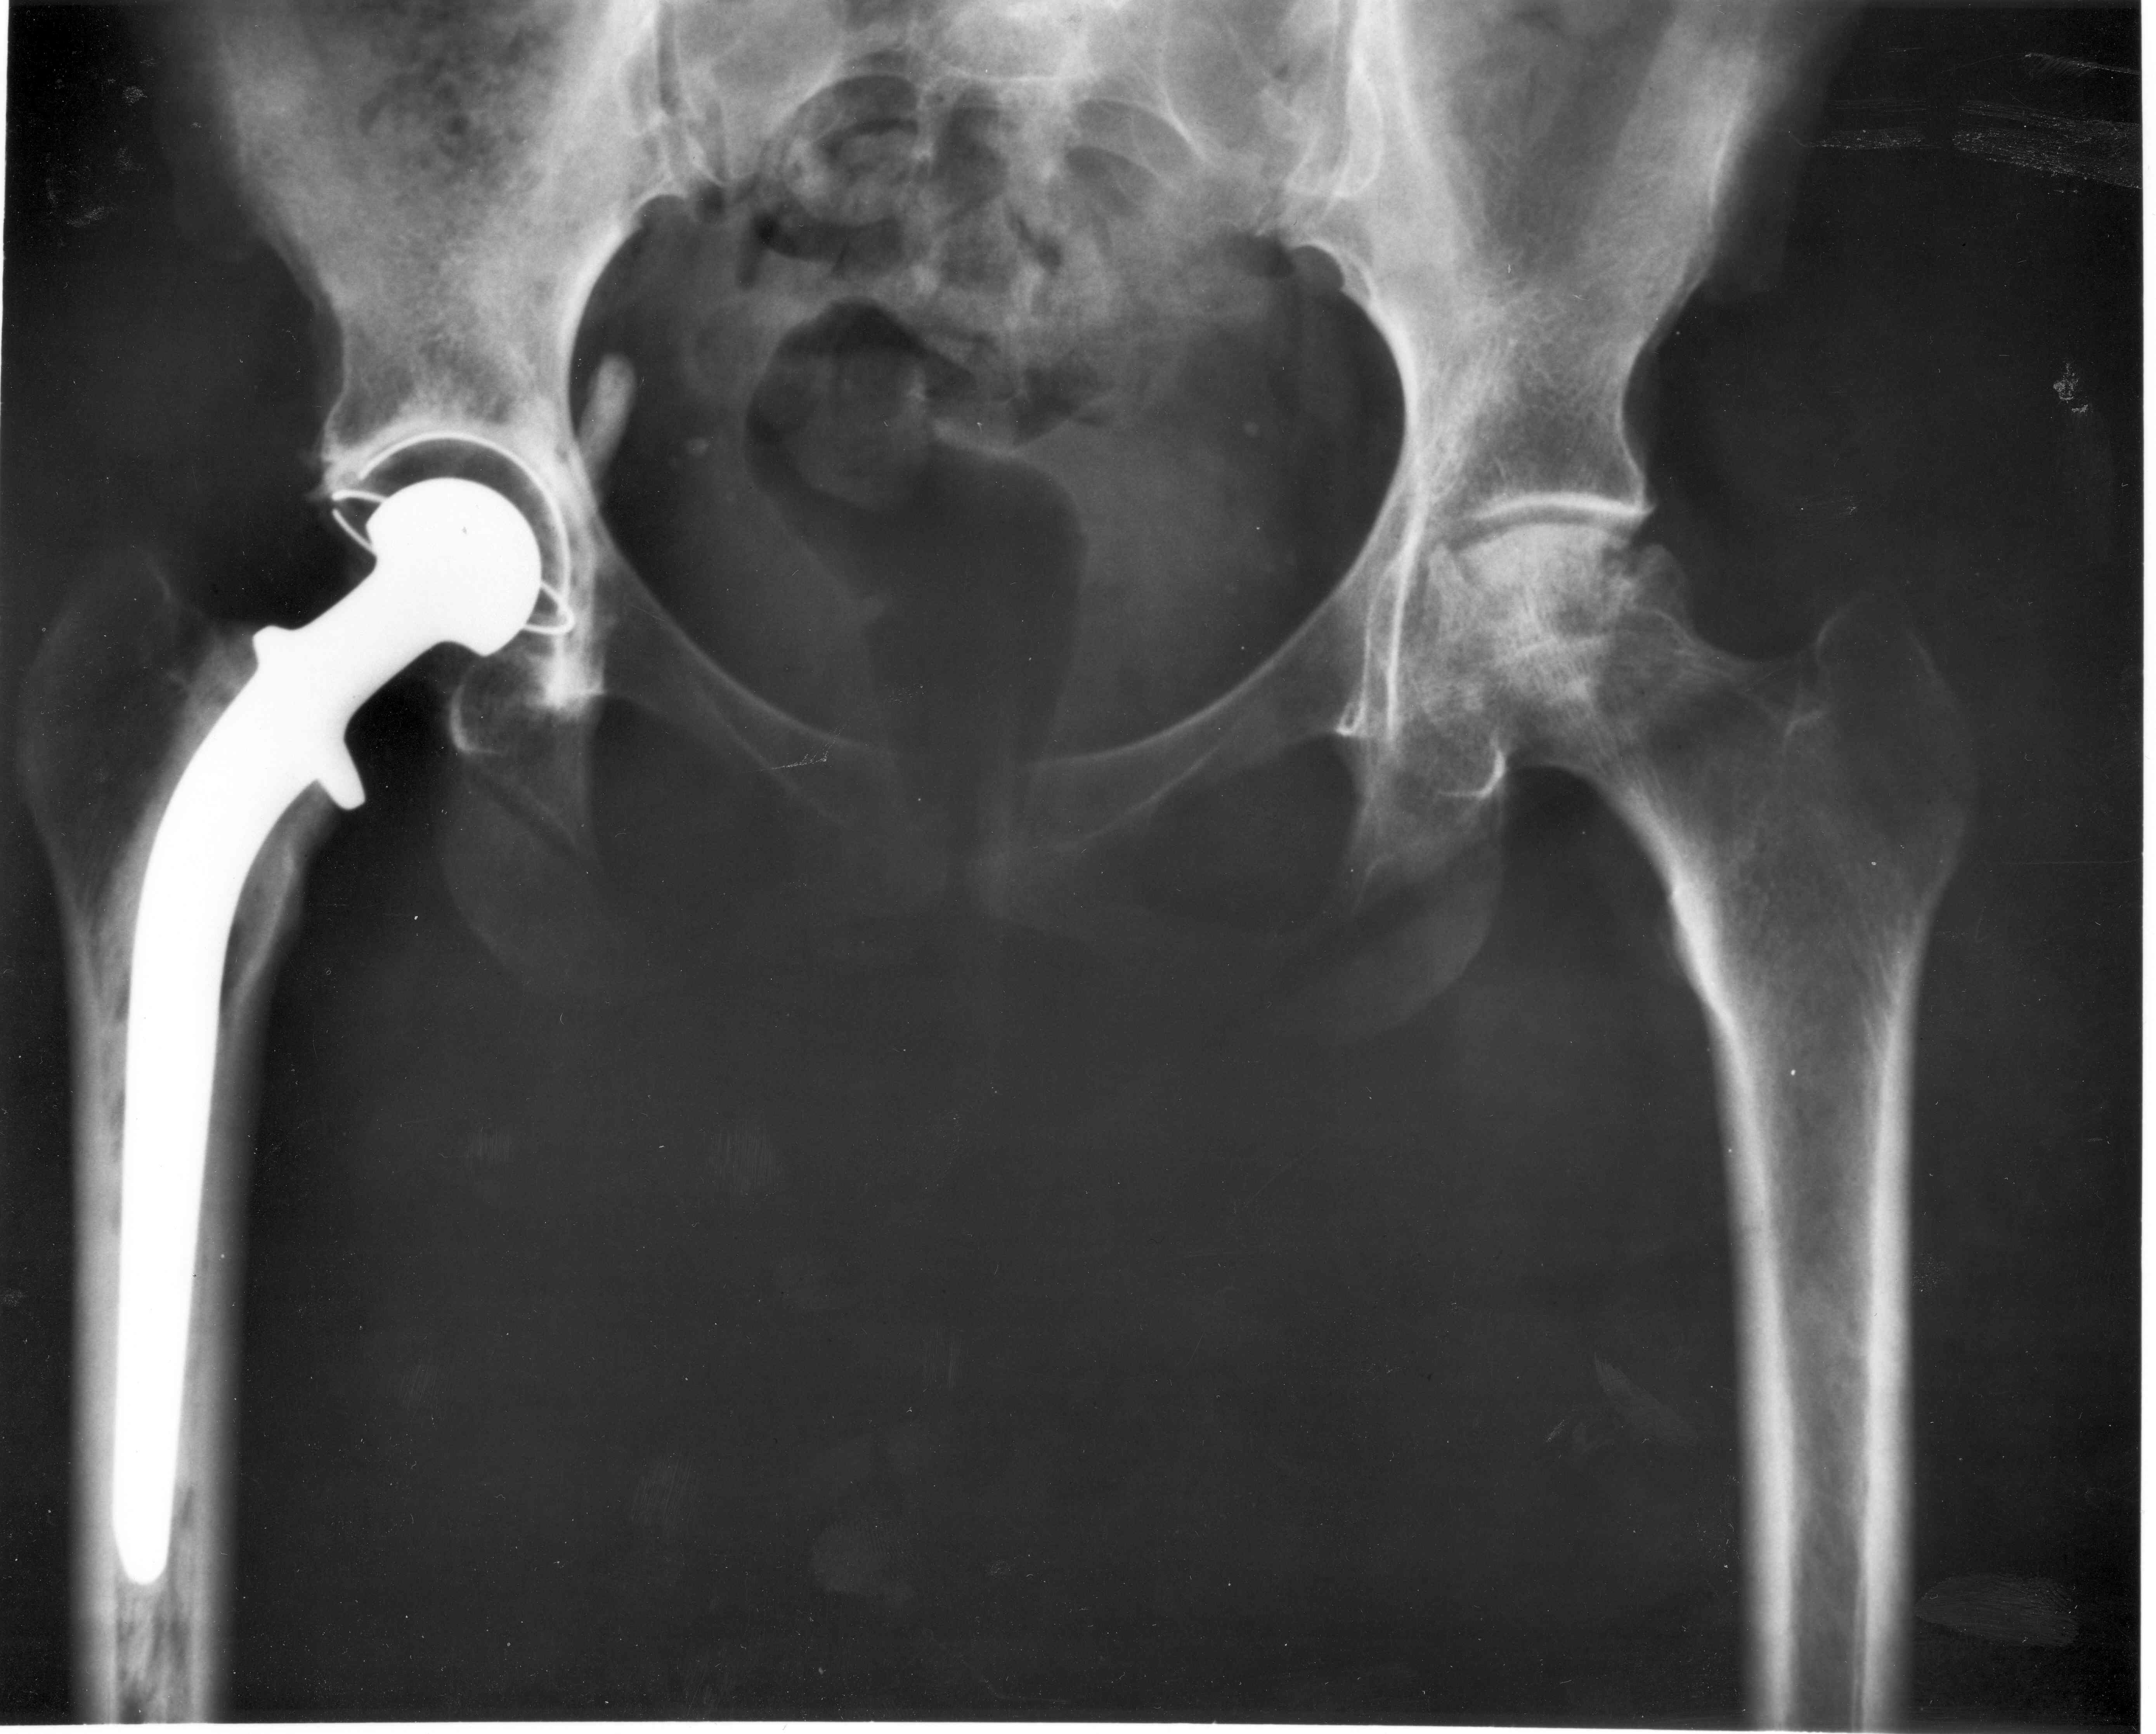

- Radiografías.

En la mayoría de los casos, las pruebas radiológicas como los rayos X son suficientes para confirmar la displasia de cadera. No obstante, siempre se recomienda complementar los estudios para descartar problemas secundarios.

- Tratamiento quirúrgico: intervención clínica que consiste en reconstruir, reorientar y corregir la subluxación o luxación completa que exista. En casos más graves, se podría optar por el reemplazo completo de la cadera, aunque el costo del proceso es bastante elevado.

Cabe resaltar que aunque el tratamiento quirúrgico repara por completo el problema actual, no impide que la degeneración vuelva a aparecer. Por esta razón, solo se recomienda en los gatos adultos con casos severos de displasias de cadera.